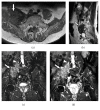

Magnetic resonance neurography is a high-resolution imaging technique that allows evaluating different neurological pathologies in correlation to clinical and the electrophysiological data. The aim of this article is to present a review on the anatomy of the lumbosacral plexus nerves, along with imaging protocols, interpretation pitfalls, and most common pathologies that should be recognized by the radiologist: traumatic, iatrogenic, entrapment, tumoral, infectious, and inflammatory conditions. An extensive series of clinical and imaging cases is presented to illustrate key-points throughout the article.